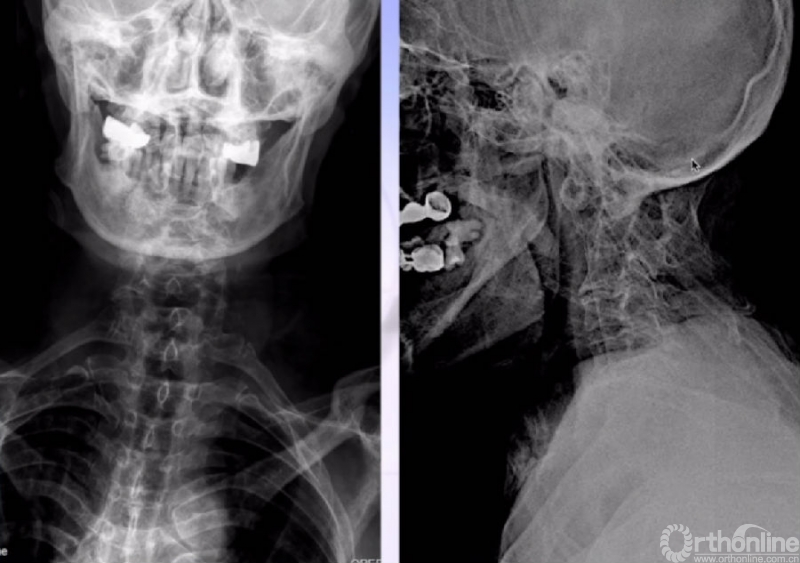

X线正、侧位

MRI

CT

CTA